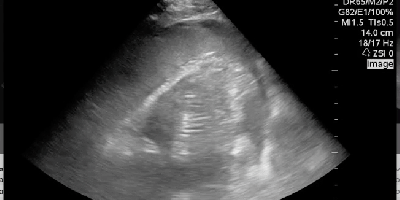

Global Ultrasound, Make the POCUS diagnosis, Sono Instruction, sono of the week, Sono Stuff